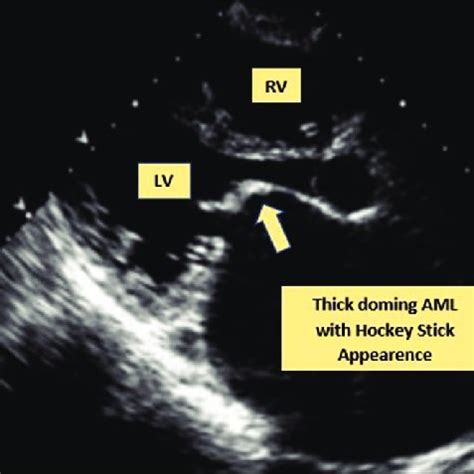

The Microscopic View: What is the Hockey Stick Appearance?

So, what exactly are we looking at when we talk about the hockey stick appearance in the context of Acute Myeloid Leukemia (AML)? Imagine peering through a powerful microscope at a sample of bone marrow or peripheral blood. You’re looking for abnormal cells, known as blast cells, which are immature white blood cells that have gone rogue in AML. Normally, these cells would mature into functional white blood cells, but in AML, they accumulate and don’t mature properly. The hockey stick shape is a specific morphological characteristic that some of these blast cells can display. It’s not just a vague resemblance; it’s quite distinctive. Typically, the nucleus of the blast cell appears elongated and curved, often with a deep indentation or fold. Think of the shaft of a hockey stick. Then, the cytoplasm extends from one end of this nucleus in a tail-like fashion, resembling the blade of the stick. This gives the cell a characteristic, elongated, and slightly hooked appearance. It’s important to understand that not all blast cells in an AML patient will show this morphology, and it’s not present in every single case of AML. However, when it is seen, it’s a significant finding for the hematopathologist. This specific shape is thought to arise from abnormalities in the cell’s cytoskeleton and nuclear structure , which are common features of malignant transformation. The cell loses its normal roundness and develops these irregular, elongated forms due to disruptions in the proteins that maintain cell shape and organization. The presence of the hockey stick appearance can sometimes suggest a particular lineage of AML, most commonly those with monocytic differentiation . This includes subtypes like acute monocytic leukemia (AMoL) or acute myelomonocytic leukemia (AMML). In these types of AML, the myeloid precursors have a tendency to develop more irregular and folded nuclear shapes, making the hockey stick morphology a more frequent observation. Recognizing this shape is crucial because it adds another piece to the diagnostic puzzle. It reinforces the presence of leukemic blasts and can help guide the pathologist in classifying the specific subtype of AML. This classification is absolutely critical, guys, because different subtypes of AML respond differently to various treatments. So, while we have advanced genetic and molecular tests today, the fundamental skill of recognizing classic morphological features like the hockey stick appearance remains a cornerstone of AML diagnosis. It’s a visual hallmark that, when identified by an experienced pathologist, provides valuable information that complements other diagnostic data, leading to more accurate and timely diagnoses and ultimately, better patient care. The detailed examination of cells under a microscope is a skill that has been refined over decades, and these classic descriptions, like the hockey stick appearance, are part of the specialized language pathologists use to describe and classify blood disorders. It’s a testament to the power of observation in medicine.